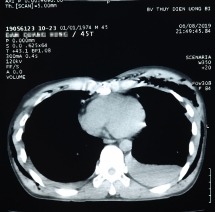

Nam thanh niên được chỉ định chụp phim cắt lớp vi tính lồng ngực, kết quả cho thấy: Tràn khí, tràn dịch màng phổi trái, máu chảy ồ ạt.

Khi đang làm việc bị đất đổ đè vào lưng, người bệnh bị gãy nhiều xương sườn, gãy xương đòn phải, xương bả vai phải và tràn máu, tràn khí màng phổi 2 bên.